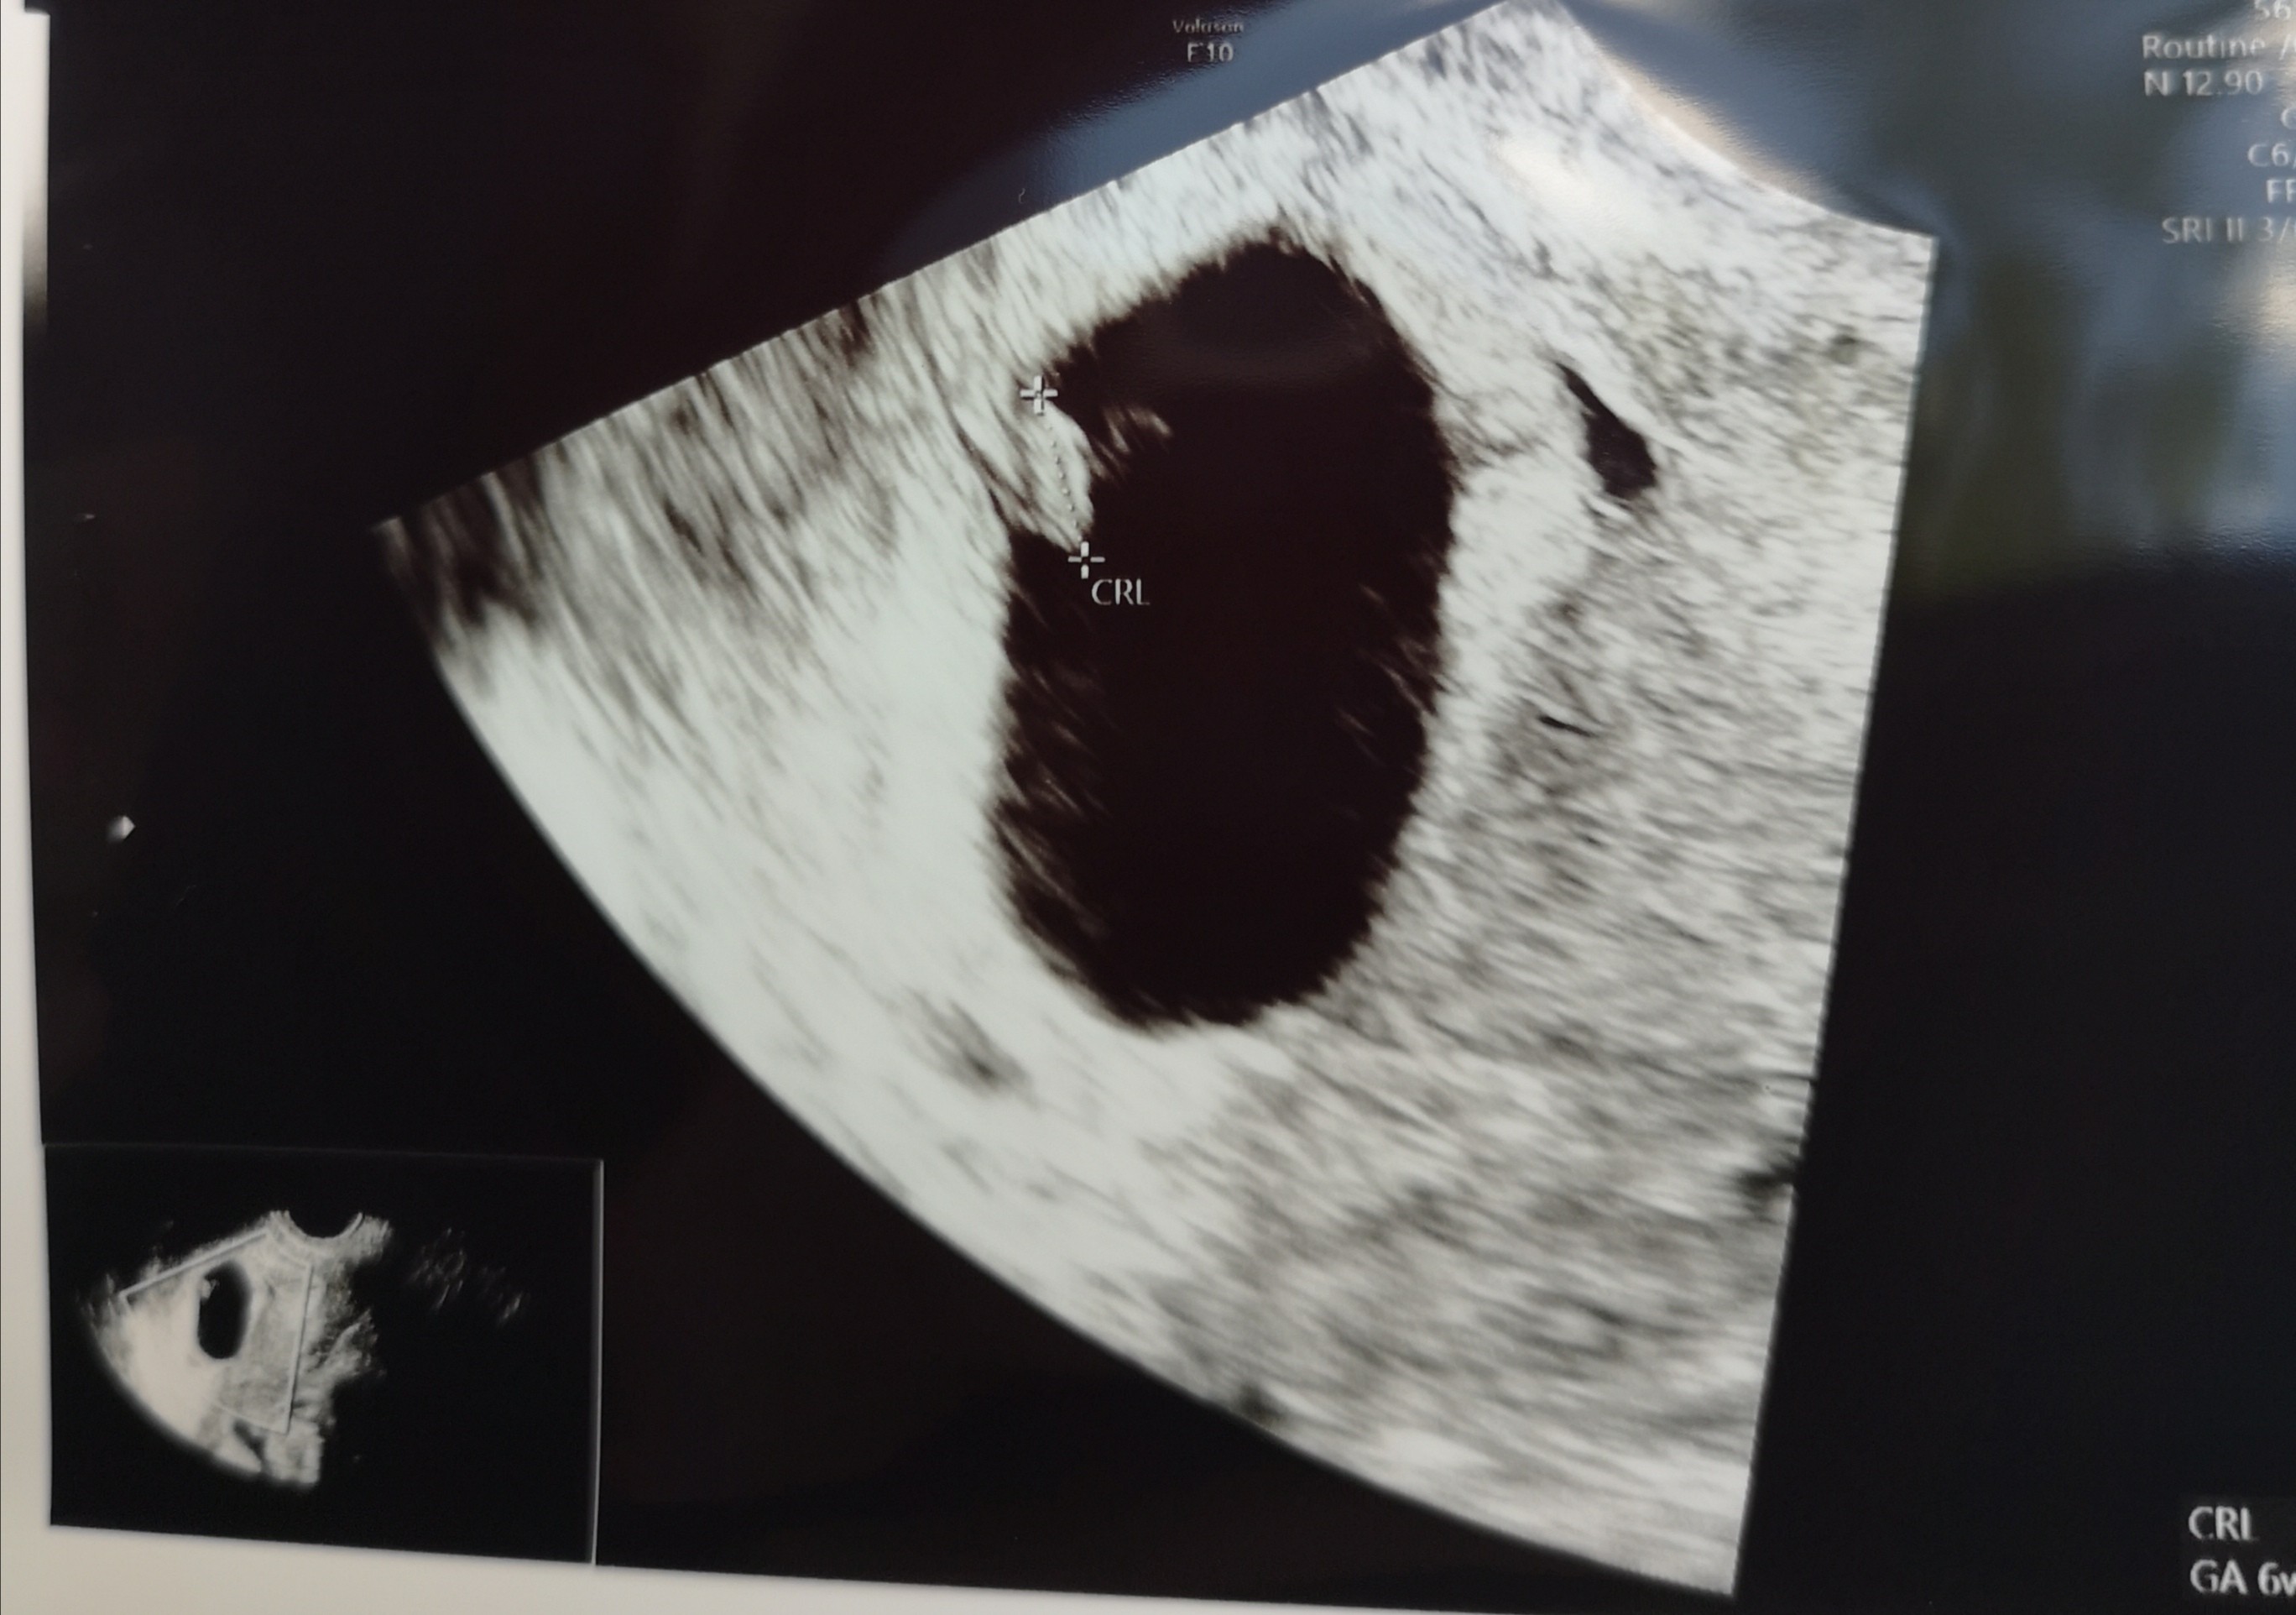

Hej, juz po wizycie [emoji3059][emoji3059] wszystko jest ok, dzidziuś ma 63mm, tetno 118 [emoji3][emoji3] kolejna wizyta dopiero za msc [emoji87][emoji87] aa i wg usg dzis 6+3 [emoji3] termin na 10.01.22 [emoji173]️[emoji173]️

Hej, juz po wizycie [emoji3059][emoji3059] wszystko jest ok, dzidziuś ma 63mm, tetno 118 [emoji3][emoji3] kolejna wizyta dopiero za msc [emoji87][emoji87] aa i wg usg dzis 6+3 [emoji3] termin na 10.01.22 [emoji3590][emoji3590]